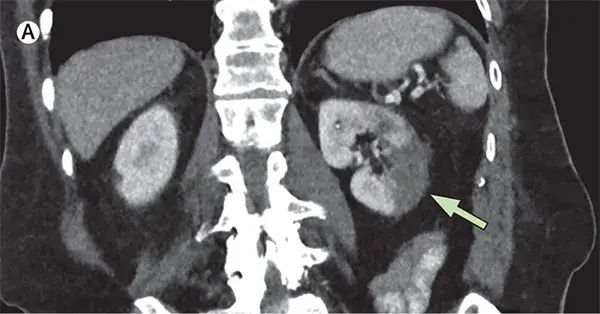

Caso muy ilustrativo publicado en Kidney 360 (enlace). Paciente de sexo femenino de 43 años con antecedentes de nefritis lúpica (NL) proliferativa durante 13 años. La paciente tenía un historial de enfermedad grave, con múltiples tratamientos que incluyeron infusiones de metilprednisolona y ciclofosfamida debido al compromiso del sistema nervioso central (SNC) y de la NL.